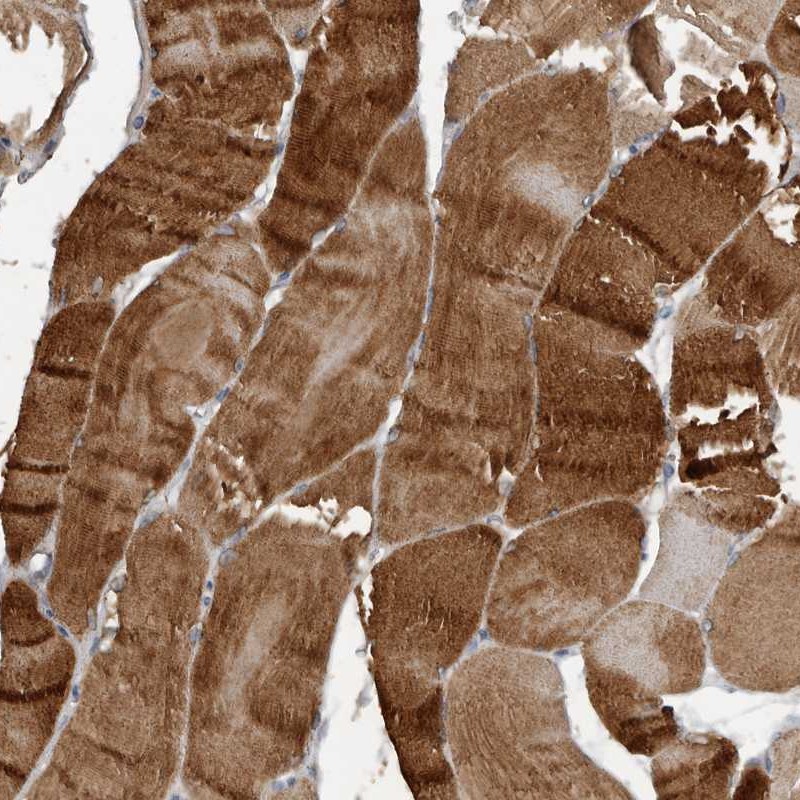

Immunohistochemical staining of human skeletal muscle shows strong cytoplasmic positivity in myocytes.